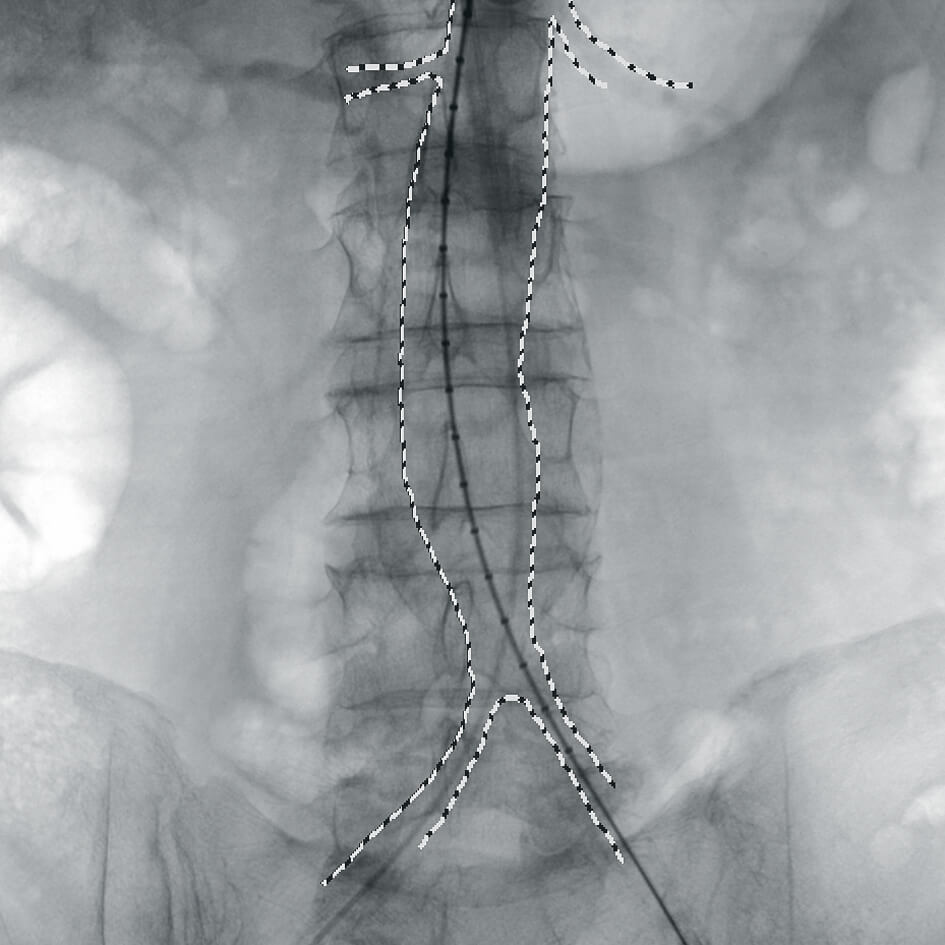

- программный пакет для сосудистой хирургии,

- субтракционная ангиография с применением СО2.

Полное отсутствие искажений снимков в сочетании с высоким динамическим диапазоном широко востребованы как при сложных операциях в нейрохирургии, сосудистой хирургии, инвазивной радиологии, так и в гибридных областях применения, а также в ортопедии, травматологии. В сосудистой хирургии особенно важны высокий динамический диапазон и пространственное разрешение, обеспечивающие детальную визуализацию даже мельчайших сосудов. Специализированное программное обеспечение SmartVascular позволяет проводить настройку системы для васкулярных операций и сосудистой хирургии.